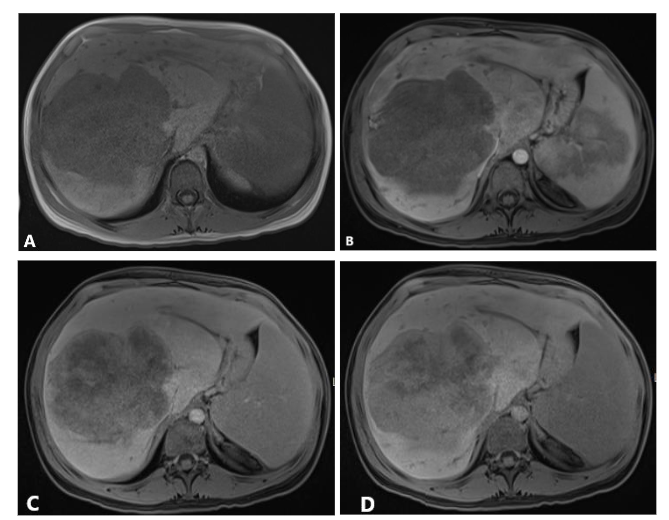

Liver biopsy confirmed the diagnosis of sclerosing epithelioid fibrosarcoma. F-FDG PET CT scan for initial staging showed mild to moderate uptake throughout the hepatic mass without evidence of distant metastatic disease (Figure 4). Subsequently, the patient underwent an orthotopic liver transplant. On the most recent surveillance imaging, 24 months after transplantation, no findings of disease recurrence were identified, and serum CA 19-9 remained normal.

Figure 4. Maximum intensity projection (MIP) of FDG PET (A) shows mild to moderate uptake within the hepatic mass (blue arrow heads) and otherwise normal biodistribution of the tracer throughout the body with no PET findings of distant metastasis. Fused axial images of FDG PET and CT scan (B) show the most FDG avid areas of the mass. Note a focus of calcification in the mass on the non-contrast CT scan image (arrow).